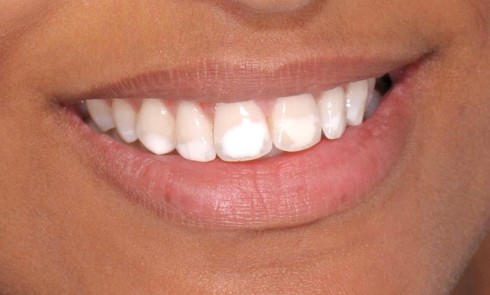

Article réservé à nos abonnés L’infiltration en profondeur – Partie II

D’autres équipes ont confirmé récemment nos premiers résultats [5, 3]. Toutefois, certaines taches n’étaient pas masquées par cette infiltration superficielle,...